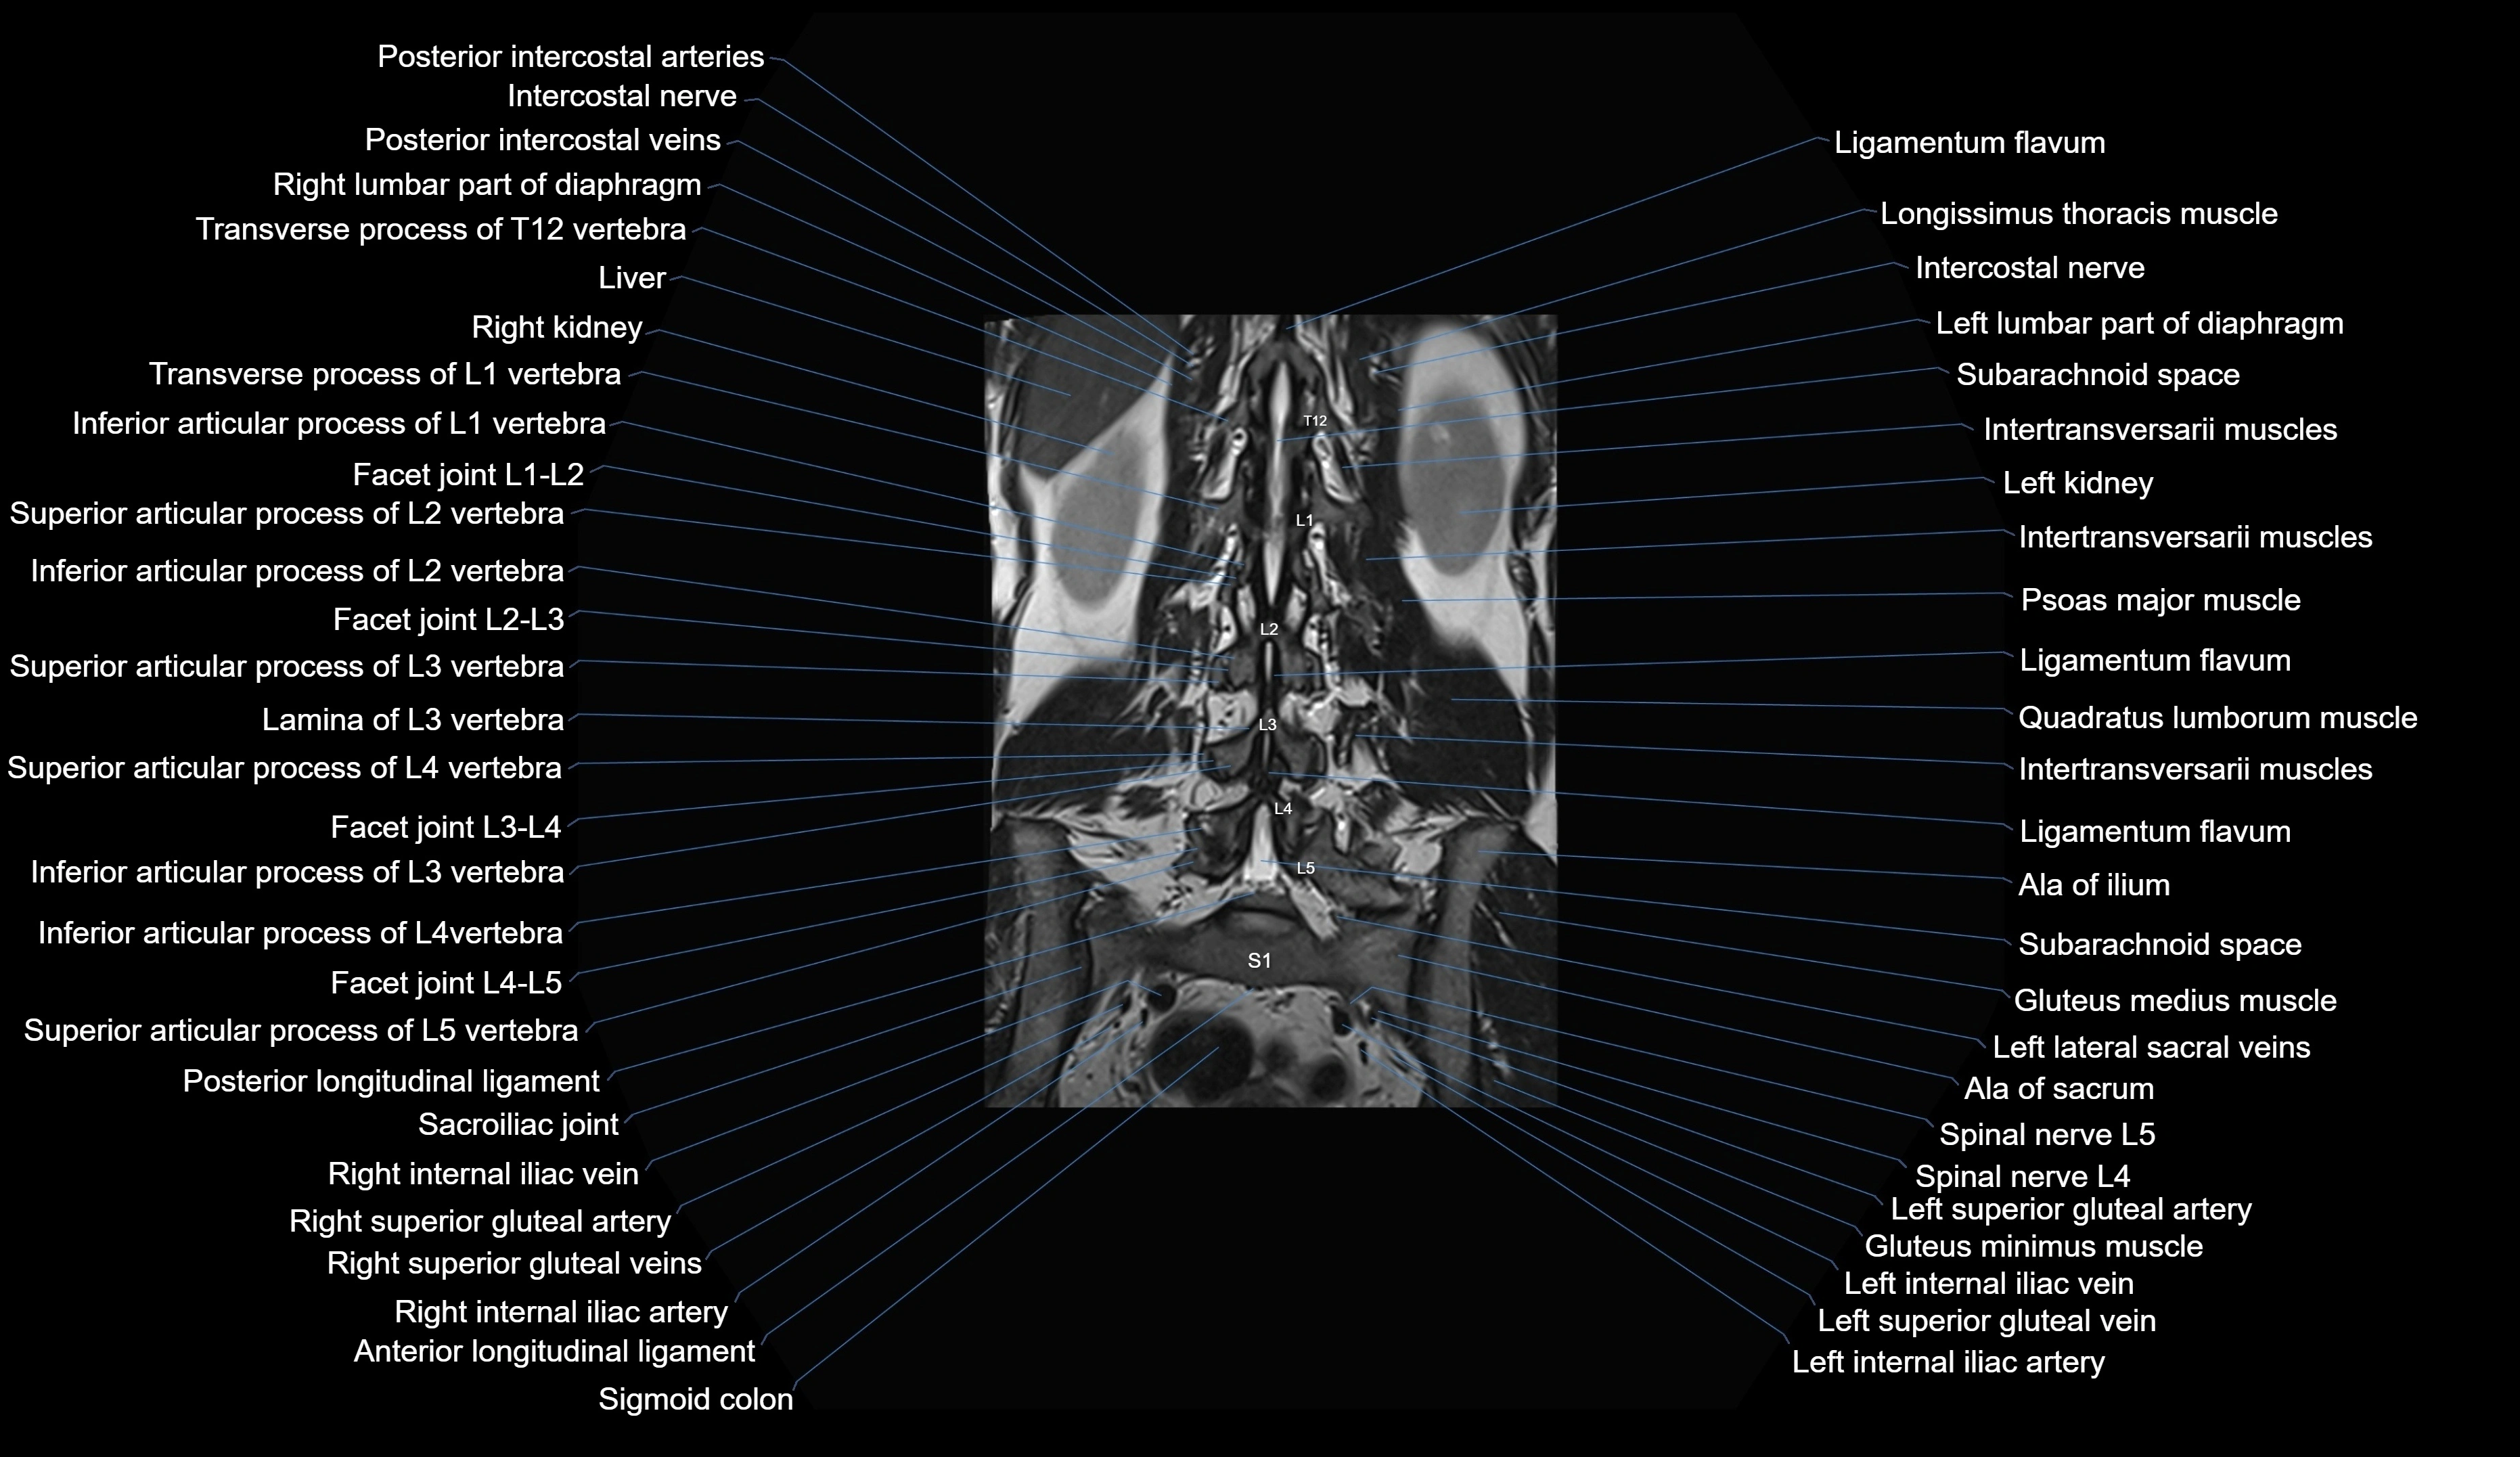

MRI images